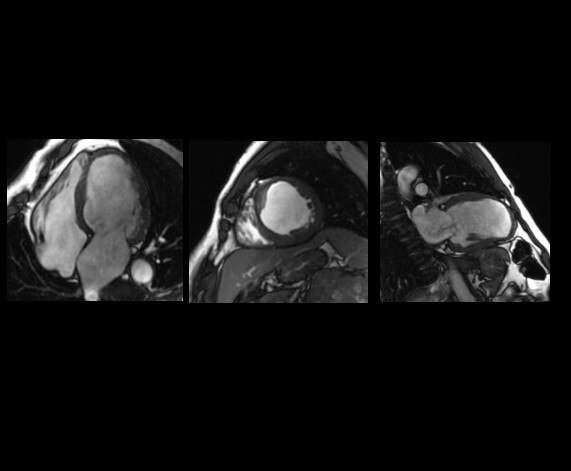

With our intuitive cardiac techniques, you can assess morphology, flow, function and tissue viability plus gain crucial insights into vascular structure and flow dynamics. CVWorks provides the flexibility to adapt to different patient types with exams that vastly simplify workflow.

With CVWorks, multi breath-hold imaging can be a thing of the past. Our latest Single shot MDE and Black Blood techniques provide patient-friendly alternatives to uncomfortable breath-holds.

With our workflow-simplified QuickStep protocols, scanning whole body vasculature can be done in less than 6 minutes. High performance gradients allow bright blood pool and myocardial tissue contrast on Cine FIESTA while preserving spatial resolution.NeuroWorks

2D Cine FIESTA

Black Blood - SSFSE

PS MDE